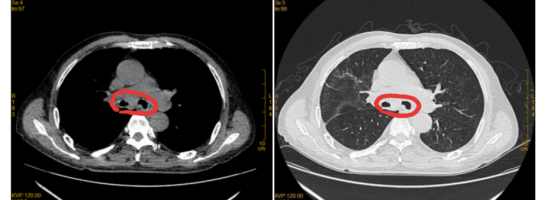

治疗前:双侧主支气管几乎被肿瘤堵死

治疗2月后:肿瘤缩小,双侧主支气管恢复通畅